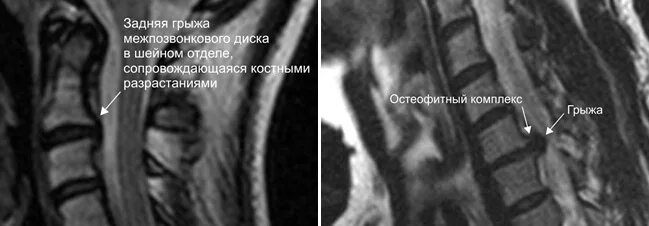

Можно ли вылечить грыжи шейные